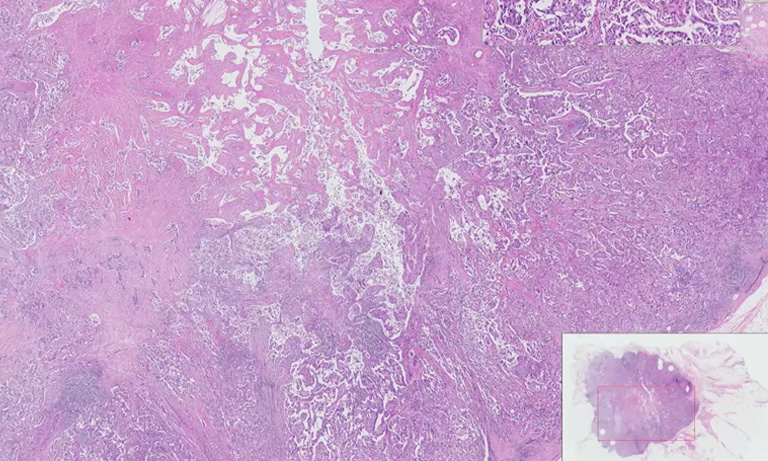

Traditional tissue research was limited to small sample areas. With whole slide imaging (WSI), you can now explore the entire specimen at multiple magnifications.

Having both brightfield and fluorescence WSI capabilities enables high-resolution digitization for spatial analysis, multiplex biomarker detection, and quantitative tissue profiling.

It delivers high-speed, high-precision scanning with exceptional image clarity and color fidelity, producing high-quality whole slide images.